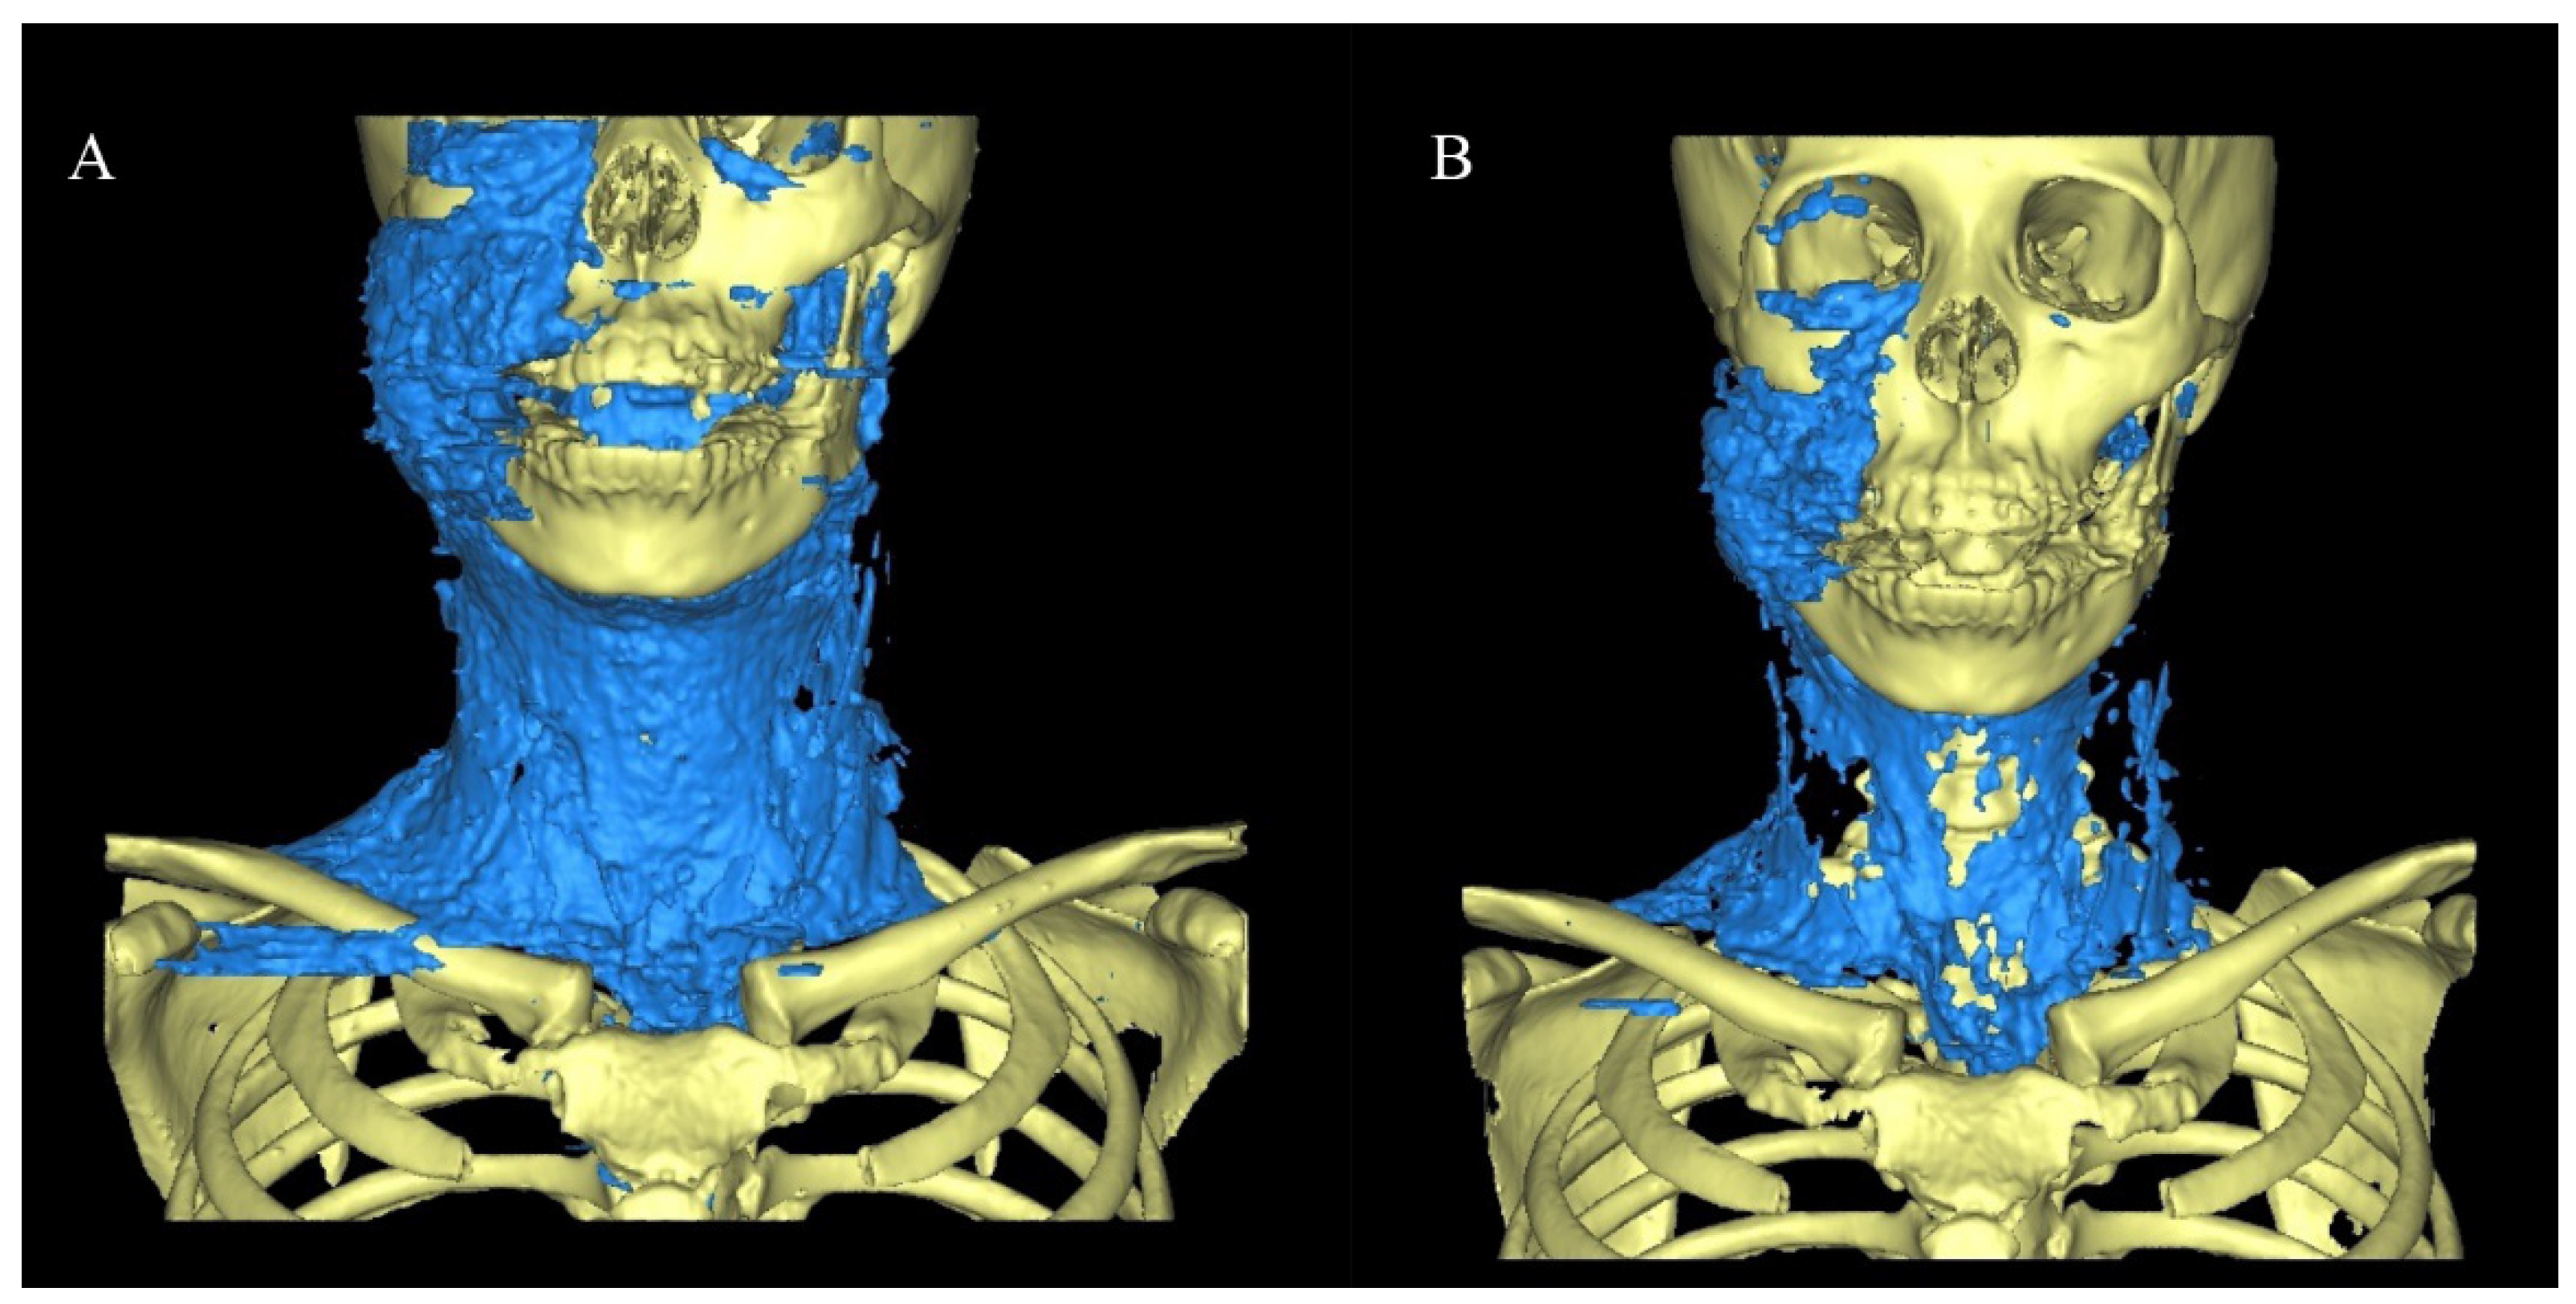

2.1. Range of Spread to Each Gap of SE

2.3.1. Case 1

2.3.2. Case 2

2.3.3. Case 3